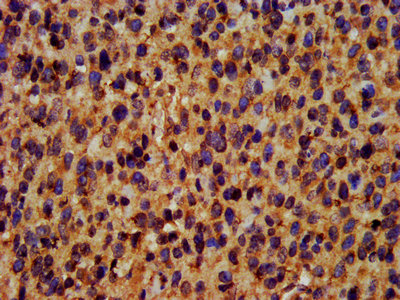

IHC (Immunohistochemistry)

(IHC image of AAA229063 diluted at 1:400 and staining in paraffin-embedded human glioma cancer performed on a Leica BondTM system. After dewaxing and hydration, antigen retrieval was mediated by high pressure in a citrate buffer (pH 6.0). Section was blocked with 10% normal goat serum 30min at RT. Then primary antibody (1% BSA) was incubated at 4 degree C overnight. The primary is detected by a biotinylated secondary antibody and visualized using an HRP conjugated SP system.)